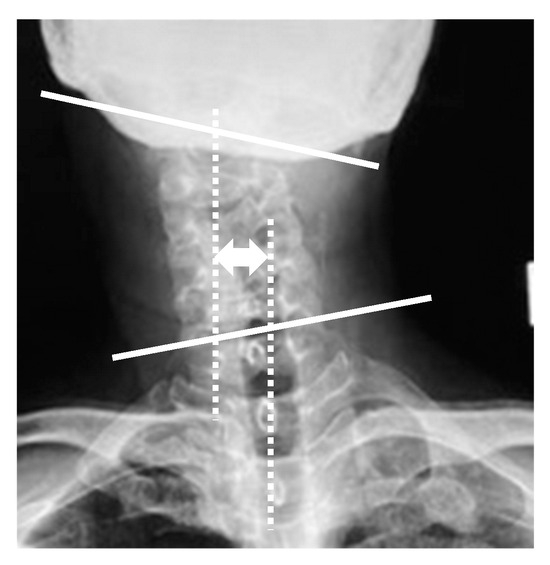

3.5. Representative Case of Bipolar Release of Sternocleidomastoid Muscle

Sixteen-year-old female. She had a history of adolescent idiopathic scoliosis. She complained of head tilt and restriction of cervical range of motion, as well as neck pain and shoulder stiffness. She presented with a markedly thickened clavicular branch of the right SCM, especially in side bending to the left side. The patient underwent a bipolar release of SCM. Her radiographic parameters improved from baseline to final follow-up: CMA from 16° to 4°, C2 to T1 distance from 13 mm to 5 mm, clavicle angle from 4° to 1°, CSVL from 13 mm to 8 mm, cervical range of motion from 32° to 77°, and C2–7 SVA from 42 to 17 mm (Figure 3).

Figure 3.

Sixteen-year-old female was treated with the bipolar release of the sternocleidomastoid. Pre- (a,b,e,g) and postoperative (c,d,f,h) appearance, radiographs, and intraoperative photographs. The head was markedly tilted to the right side, and the neck was shifted to the left side preoperatively. Right lower ends of the sternal branch and clavicular branch of the sternocleidomastoid (SCM) were released at one incision (i,j). The upper end of the SCM was released at the other incision (k). There were good improvements in appearance and postoperative X-rays after the bipolar release of SCM.